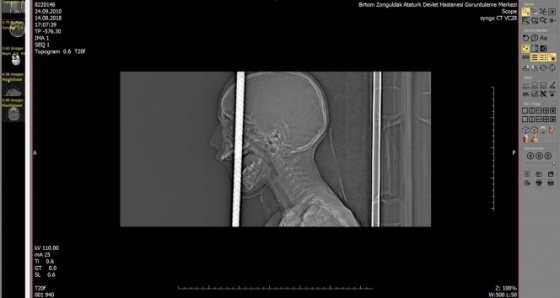

Zonguldak’ta kafasına demir saplanması sebebiyle Bülent Ecevit Üniversitesi Uygulama ve Araştırma Merkezine sevk edilen 7 yaşındaki Fırat Başaran’ın başındaki 1 metre uzunluğundaki demir çubuk, alanında uzman 7 doktor ekip tarafından 6 saat süren operasyonla çıkartıldı.

Zonguldak'ta, bisikletiyle gezerken 2 metre yükseklikten düşen 7 yaşındaki Fırat Başaran'ın ağzından giren demir başından çıktı.

Beyin cerrahisi, kulak burun boğaz, plastik cerrahisi, anestezi ve AFAD ekipleri başarılı bir ekip çalışması sonucunda 6 saat süren operasyonla 1 metre uzunluğundaki demir çubuk operasyonla alındı. Çocuk yoğun bakım ünitesine kaldırılan 7 yaşındaki Fırat Başaran’ın tedavisi devam ediyor.

Temel prensip ilk önce zarar vermeme, üst damaktan ağız içinden giren ve yaklaşık 1 metre uzunluğundaki demir çubuk kafatasını delerek sol ön fontelden 40 santim dışarı çıkmıştı.

AFAD ekipleri tarafından 3 santim kalana kadar kesildi. Temel prensiplere bağlı kalarak parçalanan bölgeyi genişleterek demir çubuk rahatlatıldı.

Sonra ameliyata alınarak demir çubuk çıkartıldı. Ön beyin düşünce davranışlarımızı yönlendirir; hafıza, düşünme, karar verme, idare etme gibi durumları evet çocuğumuz şu an yoğun bakımda bilinci açık bir şekilde zaman içinde neyi kaybettiğini görmüş olacağız.